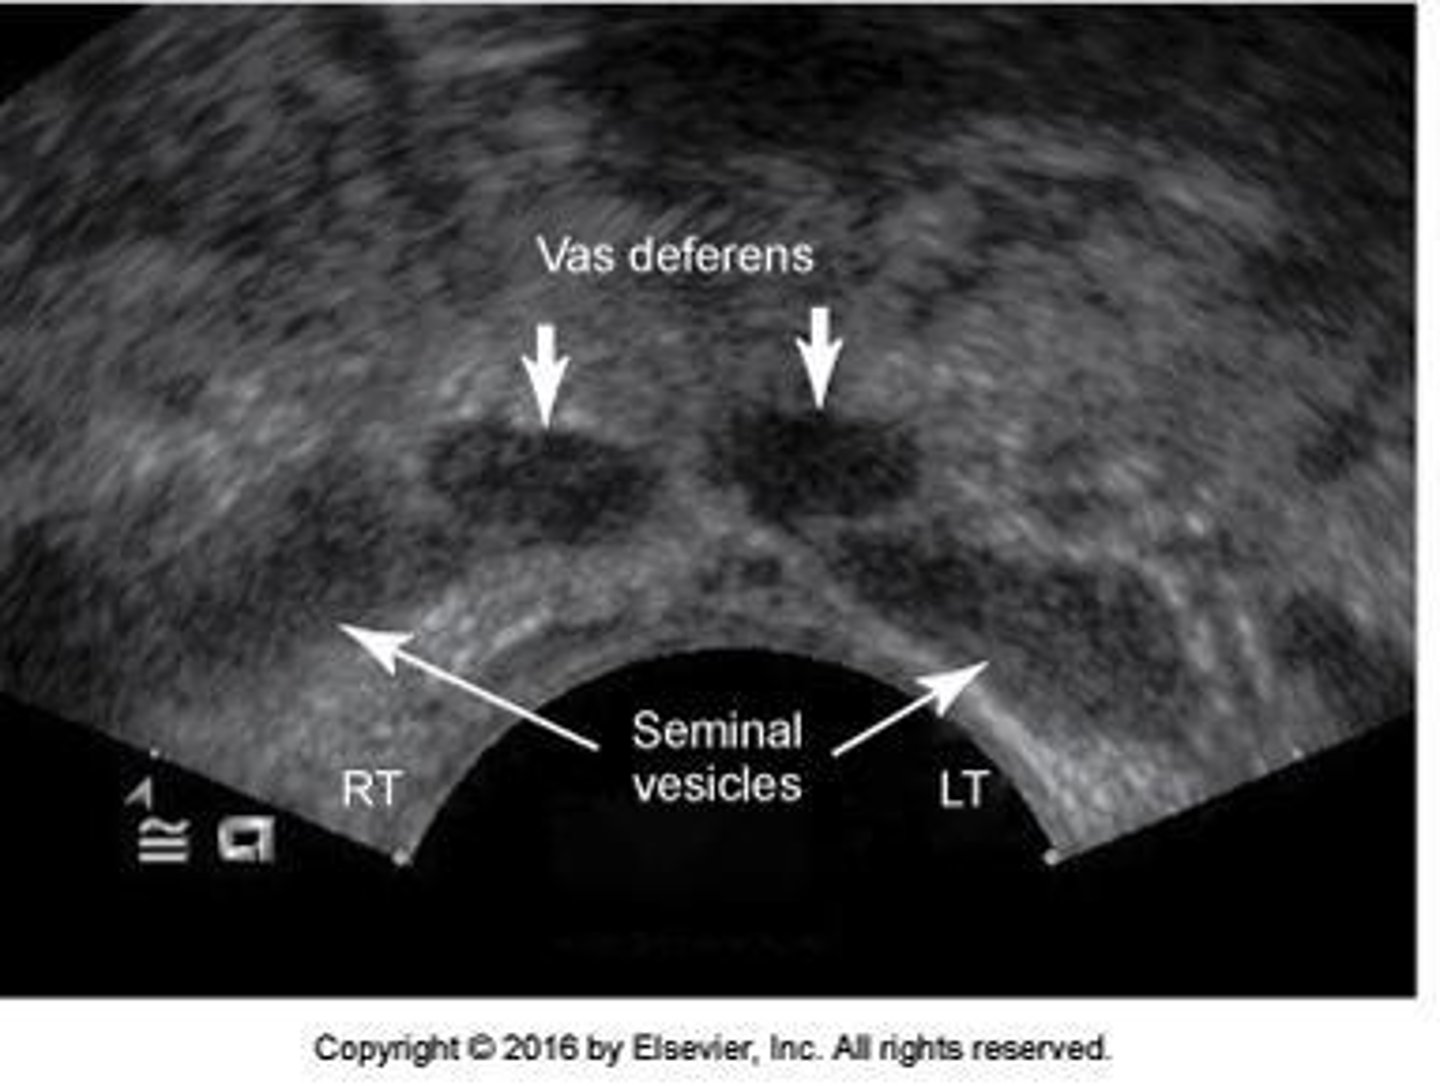

Sonographic Appearance Seminal Vesicles: _______ structures with low-level echoes superior to prostate gland

ovoid

Sonographic Appearance Seminal Vesicles: Low gray, __ structures

hypoechoic

Sonographic Appearance Seminal Vesicles: ___ in size and shape

Symmetric

Sonographic Appearance Seminal Vesicles: When scanning in the transverse plane, the seminal vesicles will be ___________________

elongated

Sonographic Appearance Seminal Vesicles: When scanning in the sagittal plane, the seminal vesicles will be ___________________

Round